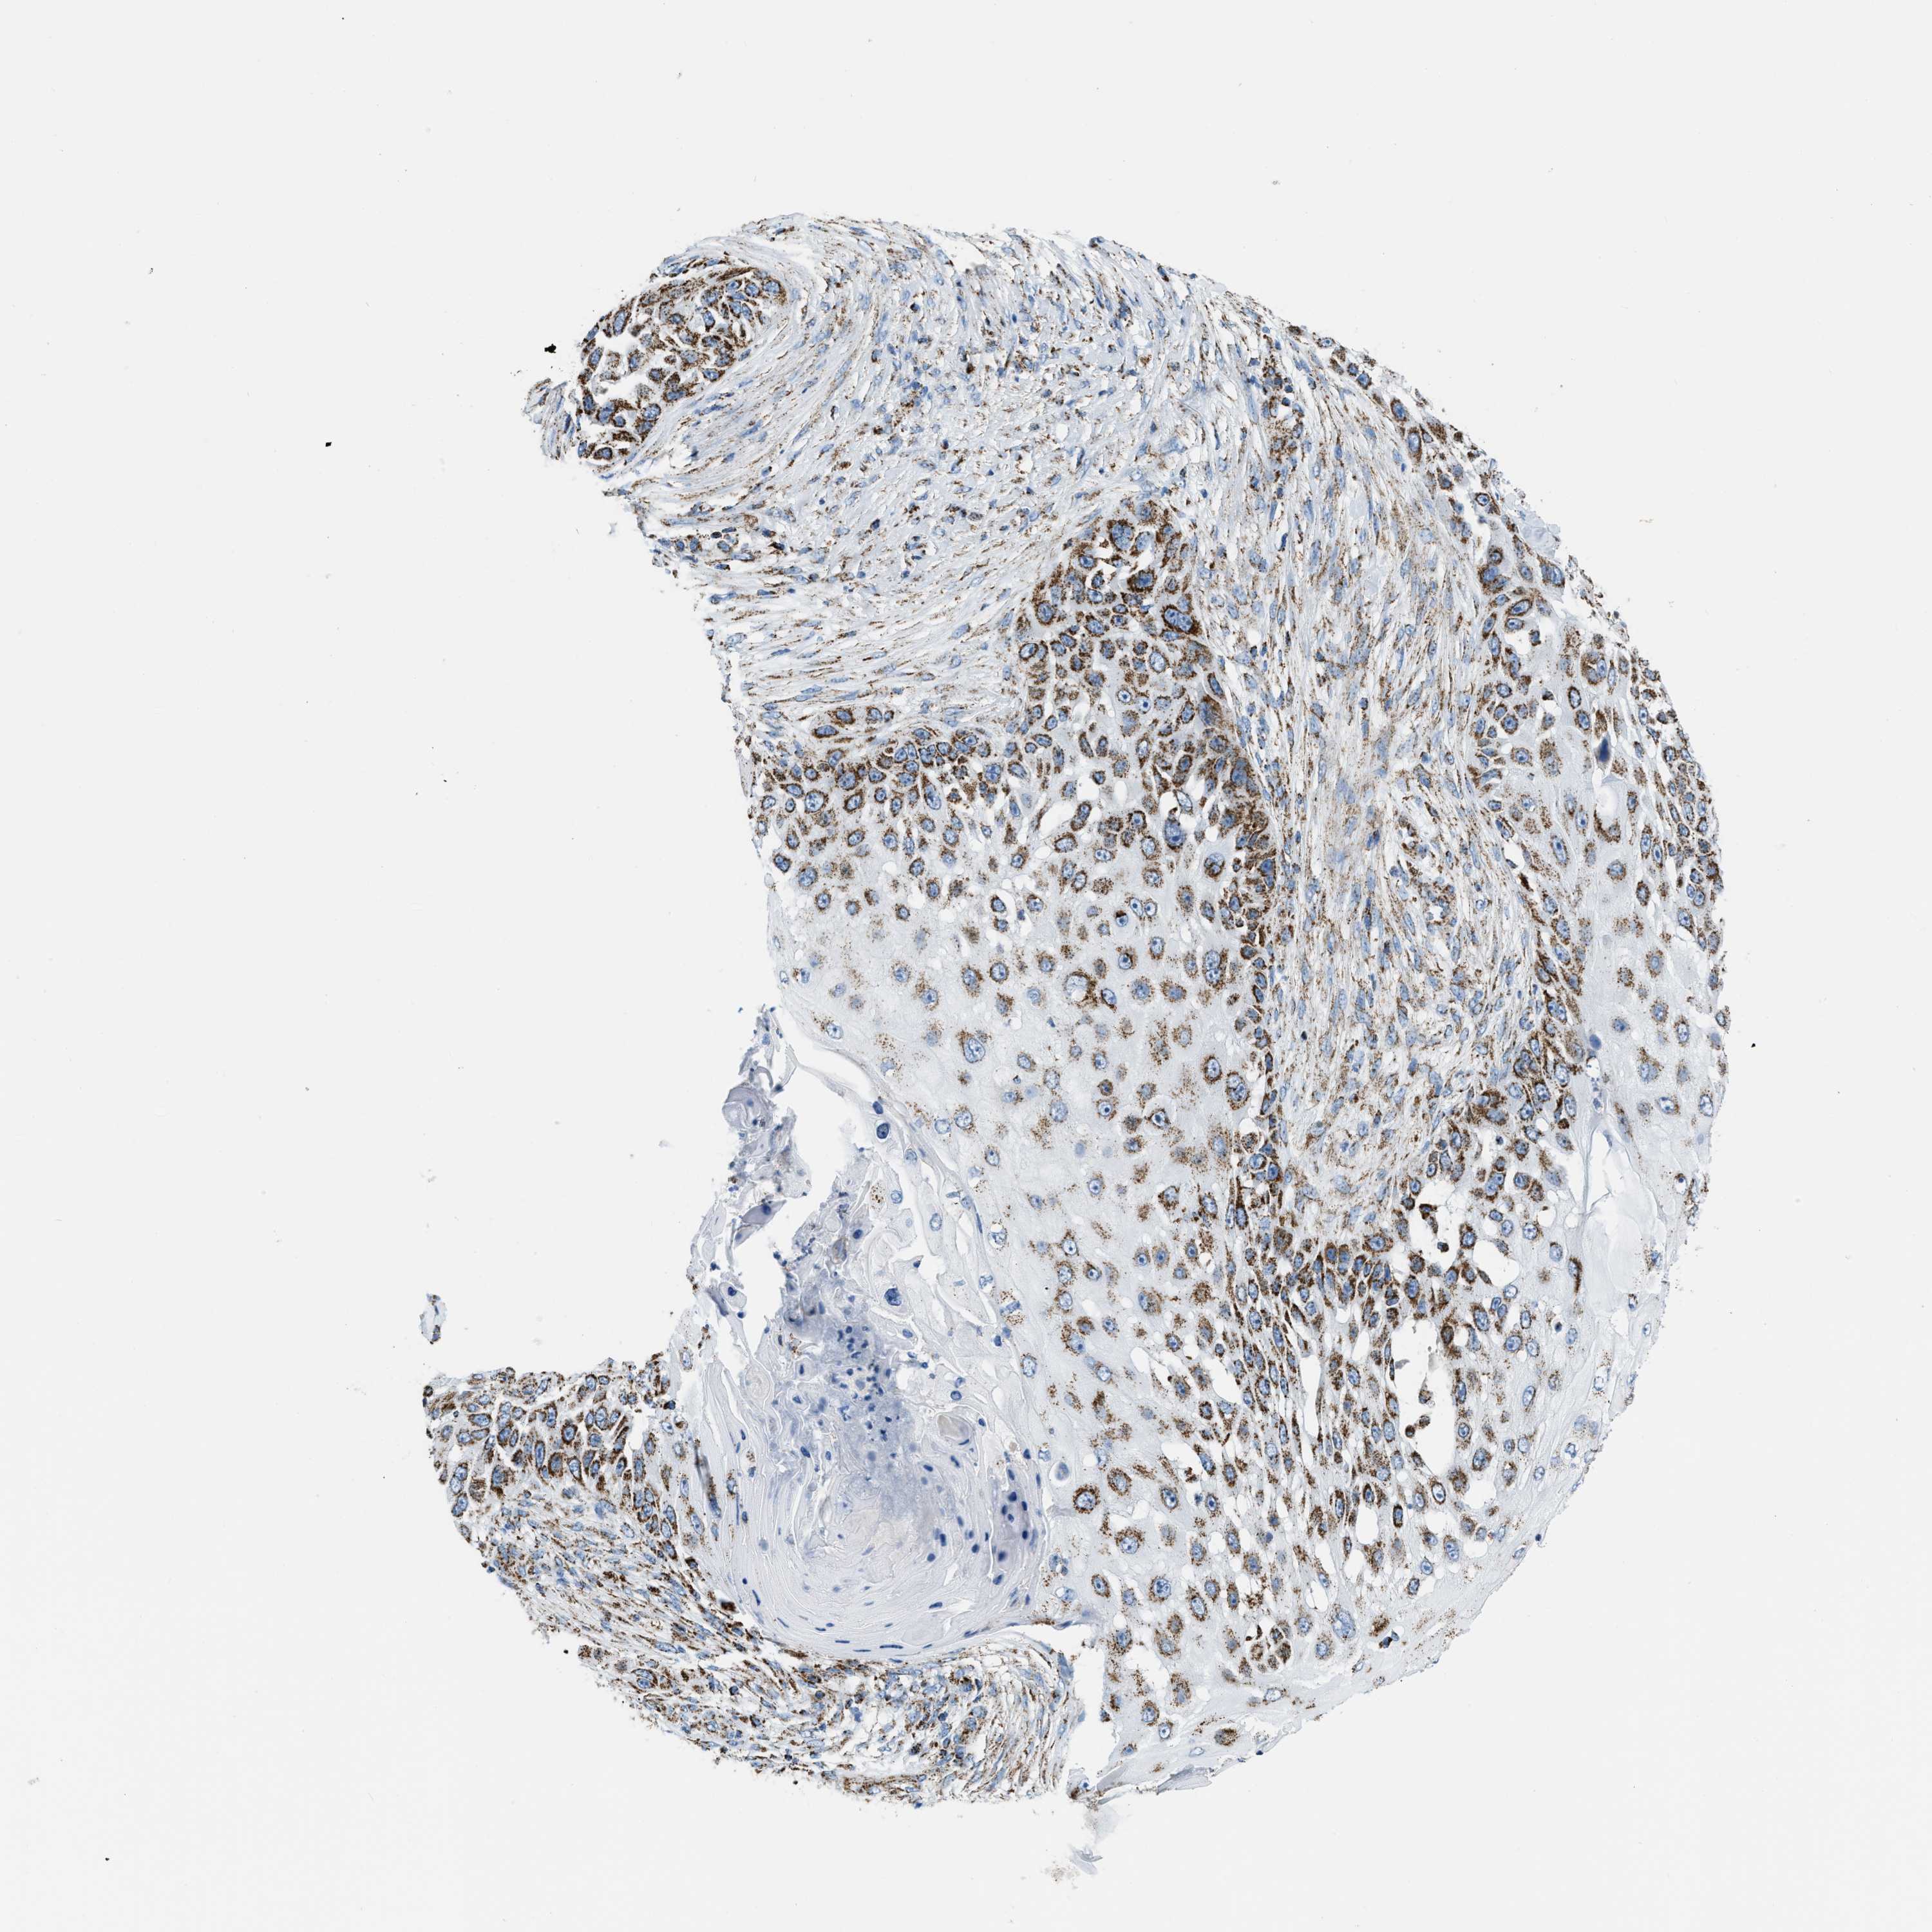

SKIN CANCER - Protein expressioni

A mouse-over function shows sample information and annotation data. Click on an image to view it in a full screen mode. Samples can be filtered based on level of antibody staining by selecting one or several of the following categories: high, medium, low and not detected. The assay and annotation is described here.

Each image is clickable and will lead to virtual microscopy that enables deeper exploration of all samples and also displays staining intensity scores, fraction scores and subcellular localization as well as patient and tissue information for each sample.

Antibody HPA018921

Squamous cell carcinoma, NOS